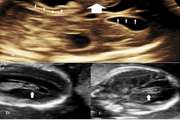

Ultrasound and magnetic resonance imaging features of fetal urogenital anomalies: A pictorial essay Jul 15 2025 - 10:59